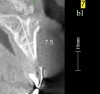

Figure 17 Volumetric characterization of the residual alveolar ridge using CBCT: Fig 17—The coronal section of the maxilla reveals the cortical structure of the alveolar ridge associated with the missing right central incisor at the mid-root level. The bu

Figure 17

Figure 18 Volumetric characterization of the residual alveolar ridge using CBCT: Fig 17—The coronal section of the maxilla reveals the cortical structure of the alveolar ridge associated with the missing right central incisor at the mid-root level. The bu

Figure 18

Figure 19 Volumetric characterization of the residual alveolar ridge using CBCT: Fig 17—The coronal section of the maxilla reveals the cortical structure of the alveolar ridge associated with the missing right central incisor at the mid-root level. The bu

Figure 19